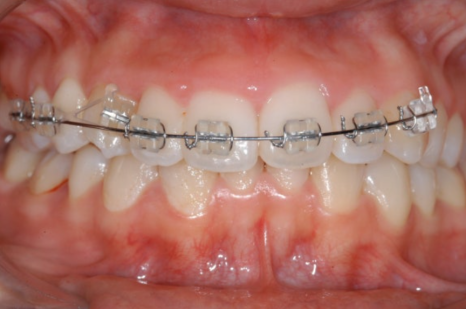

<Before-and-after orthodontic treatment photos>

Treatment period: 23.05.15 - 24.10.21 (about 1 year and 6 months)

Treatment performed: crowded teeth, alignment improvement